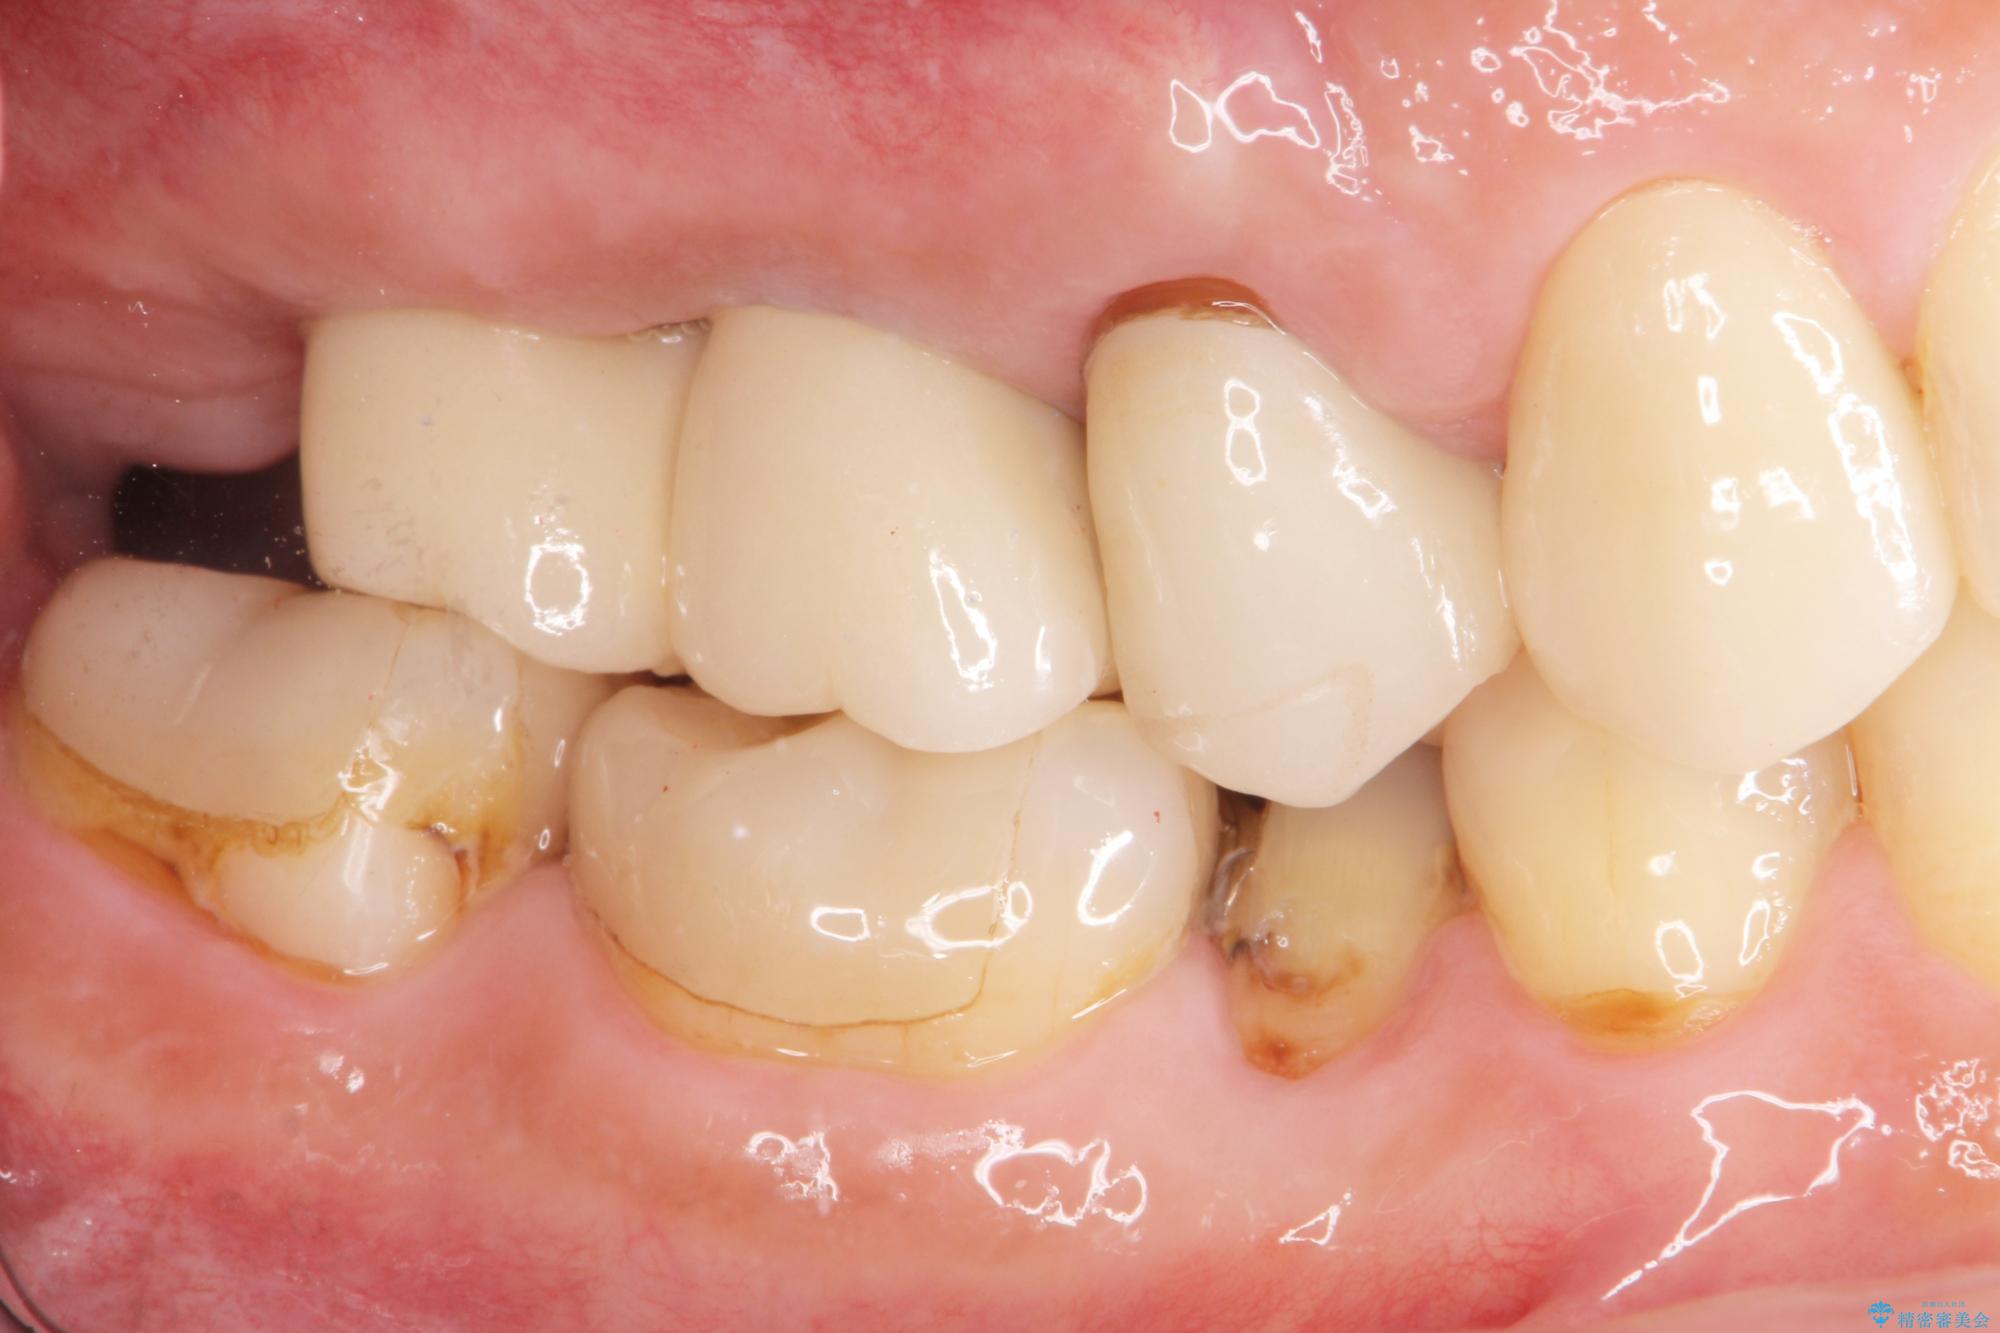

- 歯を抜いたまま放置してしまい、「やはりしっかりと噛めるような状態にしてほしい」とインプラント治療を希望され来院されました。

人工歯根であるインプラントを埋入することで奥歯でまたしっかりと噛める咬合機能を回復します。